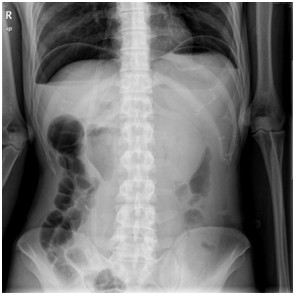

05卷-5.某急腹癥患者,其腹平片提示(本題滿分2.00分)

本題答案:C

【該題針對(duì)“ X線-消化道穿孔 ”知識(shí)點(diǎn)進(jìn)行考核】